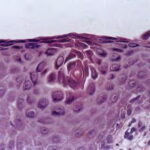

Histopathology. The earliest change consists of acantholysis in the upper epidermis, within or adjacent to the granular layer, leading to a subcorneal bulla in some instances . More commonly, enlargement of the cleft leads to detachment |

of the stratum corneum without bulla being seen. The number of acantholytic keratinocytes is usually small, often requiring a careful search to identify them. Secondary clefts may develop, leading to detachment of the epidermis in its mid level. These clefts may extend to above the basal layer, rarely giving rise to limited areas of suprabasal separation. In the setting of a subcomeal blister, dyskeratotic granular keratinocytes are diagnostic for this disorder. Eosinophilic spongiosis may be prominent with intraepidermal eosinophilic pustules. Thus, the histologic features of pemphigus foliaceus may have three pattems: {a} eosinophilic spongiosis; {b} a subcorneal blister, often with few acantholytic keratinocytes; and {c} a subcorneal blister with dyskeratotic granular keratinocytes , diagnostic of this disorder. The character of the inflammatory infiltrate is variable and depends on the age of the lesion, whether a blister is present, whether the superficial portion of the epidermis has been detached, and whether there is impetiginization or necrosis of the blister roof. |

Pathogenesis. As in pemphigus vulgaris, the autoantibodies of pemphigus foliaceus are pathogenic. During the course of the disease, the antibody levels fluctuate and have some correlation with disease activity. The pemphigus foliaceus antigen, desmoglein 1, is expressed more intensely in the upper layers of the epidermis , which explains the superficial cleavage plane of pemphigus foliaceus. Interestingly, in staphylococcal scalded skin syndrome (SSSS), and its localized form bullous impetigo, the exfoliative exotoxin produced by S. aureus specifically binds and cleaves desmoglein 1, resulting in blister formation at identical levels of the epidermis as pemphigus foliaceus . In addition, desmoglein 1 is concentrated in the upper torso and is less prominent in the buccal mucosa, scalp, and lower torso, correlating with lesion distribution . |